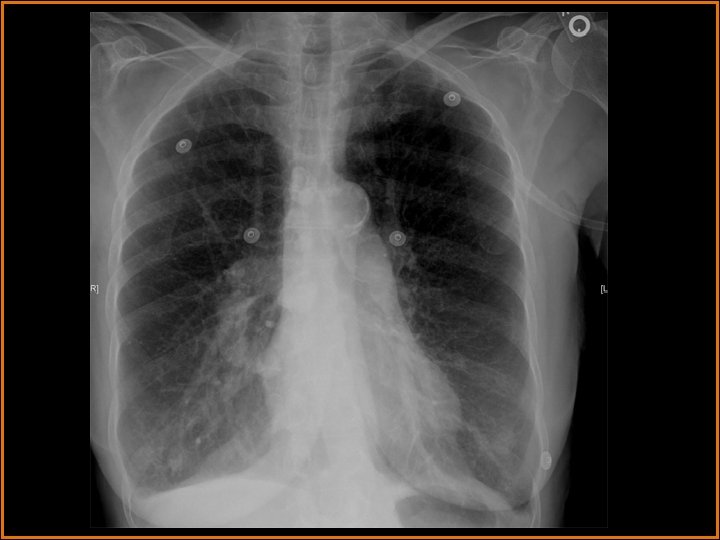

Case History 65 year old male with shortness of breath. Images: PA and Lateral View of the chest. CT of the Chest with IV contrast presented in lung windows. Please note that the images proceed from left to right and top to bottom.

Findings and Differentials Findings: The frontal view of the chest shows multiple prominent tubular structures arising from the right hilum and coursing inferiorly adjacent to the right heart border. There are multiple dilated tubular structures seen in the right lung on CT. Tubular structures within the lung are either vascular or bronchial. If bronchial, they would have to be filled with inspissated mucus to be opaque. But there are bronchi seen adjacent to these tubular structures and the bronchi are normal. The tubular structures therefore represent dilated pulmonary arteries and veins. The remainder of the right lung is normal. There also several calcified lymph nodes from prior granulomatous disease. The cardiac silhouette is normal. There are no pleural effusions. Differential: • Total Anomalous Pumonary Venous Return • Pulmonary AVM • Scimitar Syndrome

Discussion These findings are diagnostic of pulmonary AVMs are believed to be congenital defects in the terminal capillary loops that result in dilatation and formation of vascular sacs. 40 -65 percent of patients with pulmonary AVMs also have AVMs elsewhere (skin, CNS, solid organs). AVMs are seen in Osler-Weber-Rendu disease. Pumonary AVMs appear on imaging as vascular masses adjacent to the pleura or the bronchovascular bundles. They are common in the lower lobes. The draining veins are usually larger in size compared to the feeding arteries. They usually do not cause symptoms but can cause hemoptysis. Due to the right to left shunting, pulmonary AVMs are associated with cerebral abscesses. The right to left shunting also decreases the Pa. O 2 and causes the cardiac output to increase. Angiography is seldom needed to diagnose the condition. The CT findings of multiple dilated pulmonary vessels clinches the diagnosis. It is important to show the feeding artery and draining vein. Catheter embolization is the preferred treatment modality. Dilated bronchi filled with inspissated mucus can mimic this condition.